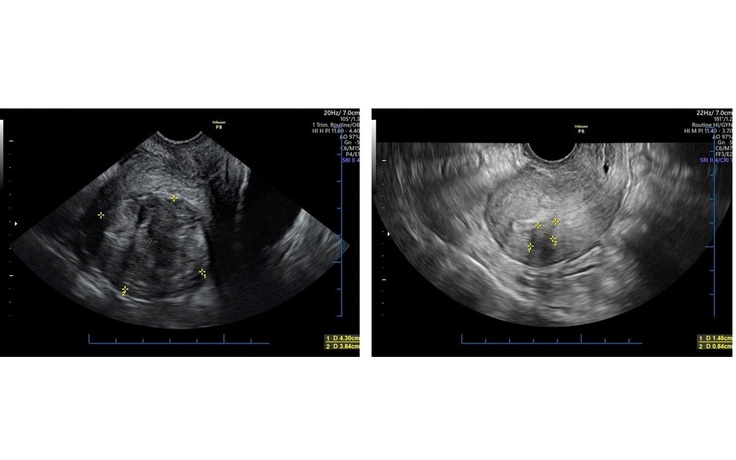

Điều trị u tử cung không xâm lấn, bảo tồn chức năng sinh sản

Theo GS-TS Nguyễn Viết Tiến, nguyên Giám đốc Bệnh viện Phụ sản T.Ư, Phó chủ tịch Tổng hội Y học VN, các khối u phụ khoa gây ảnh hưởng lớn đến sức khỏe và chất lượng sống của phụ nữ.